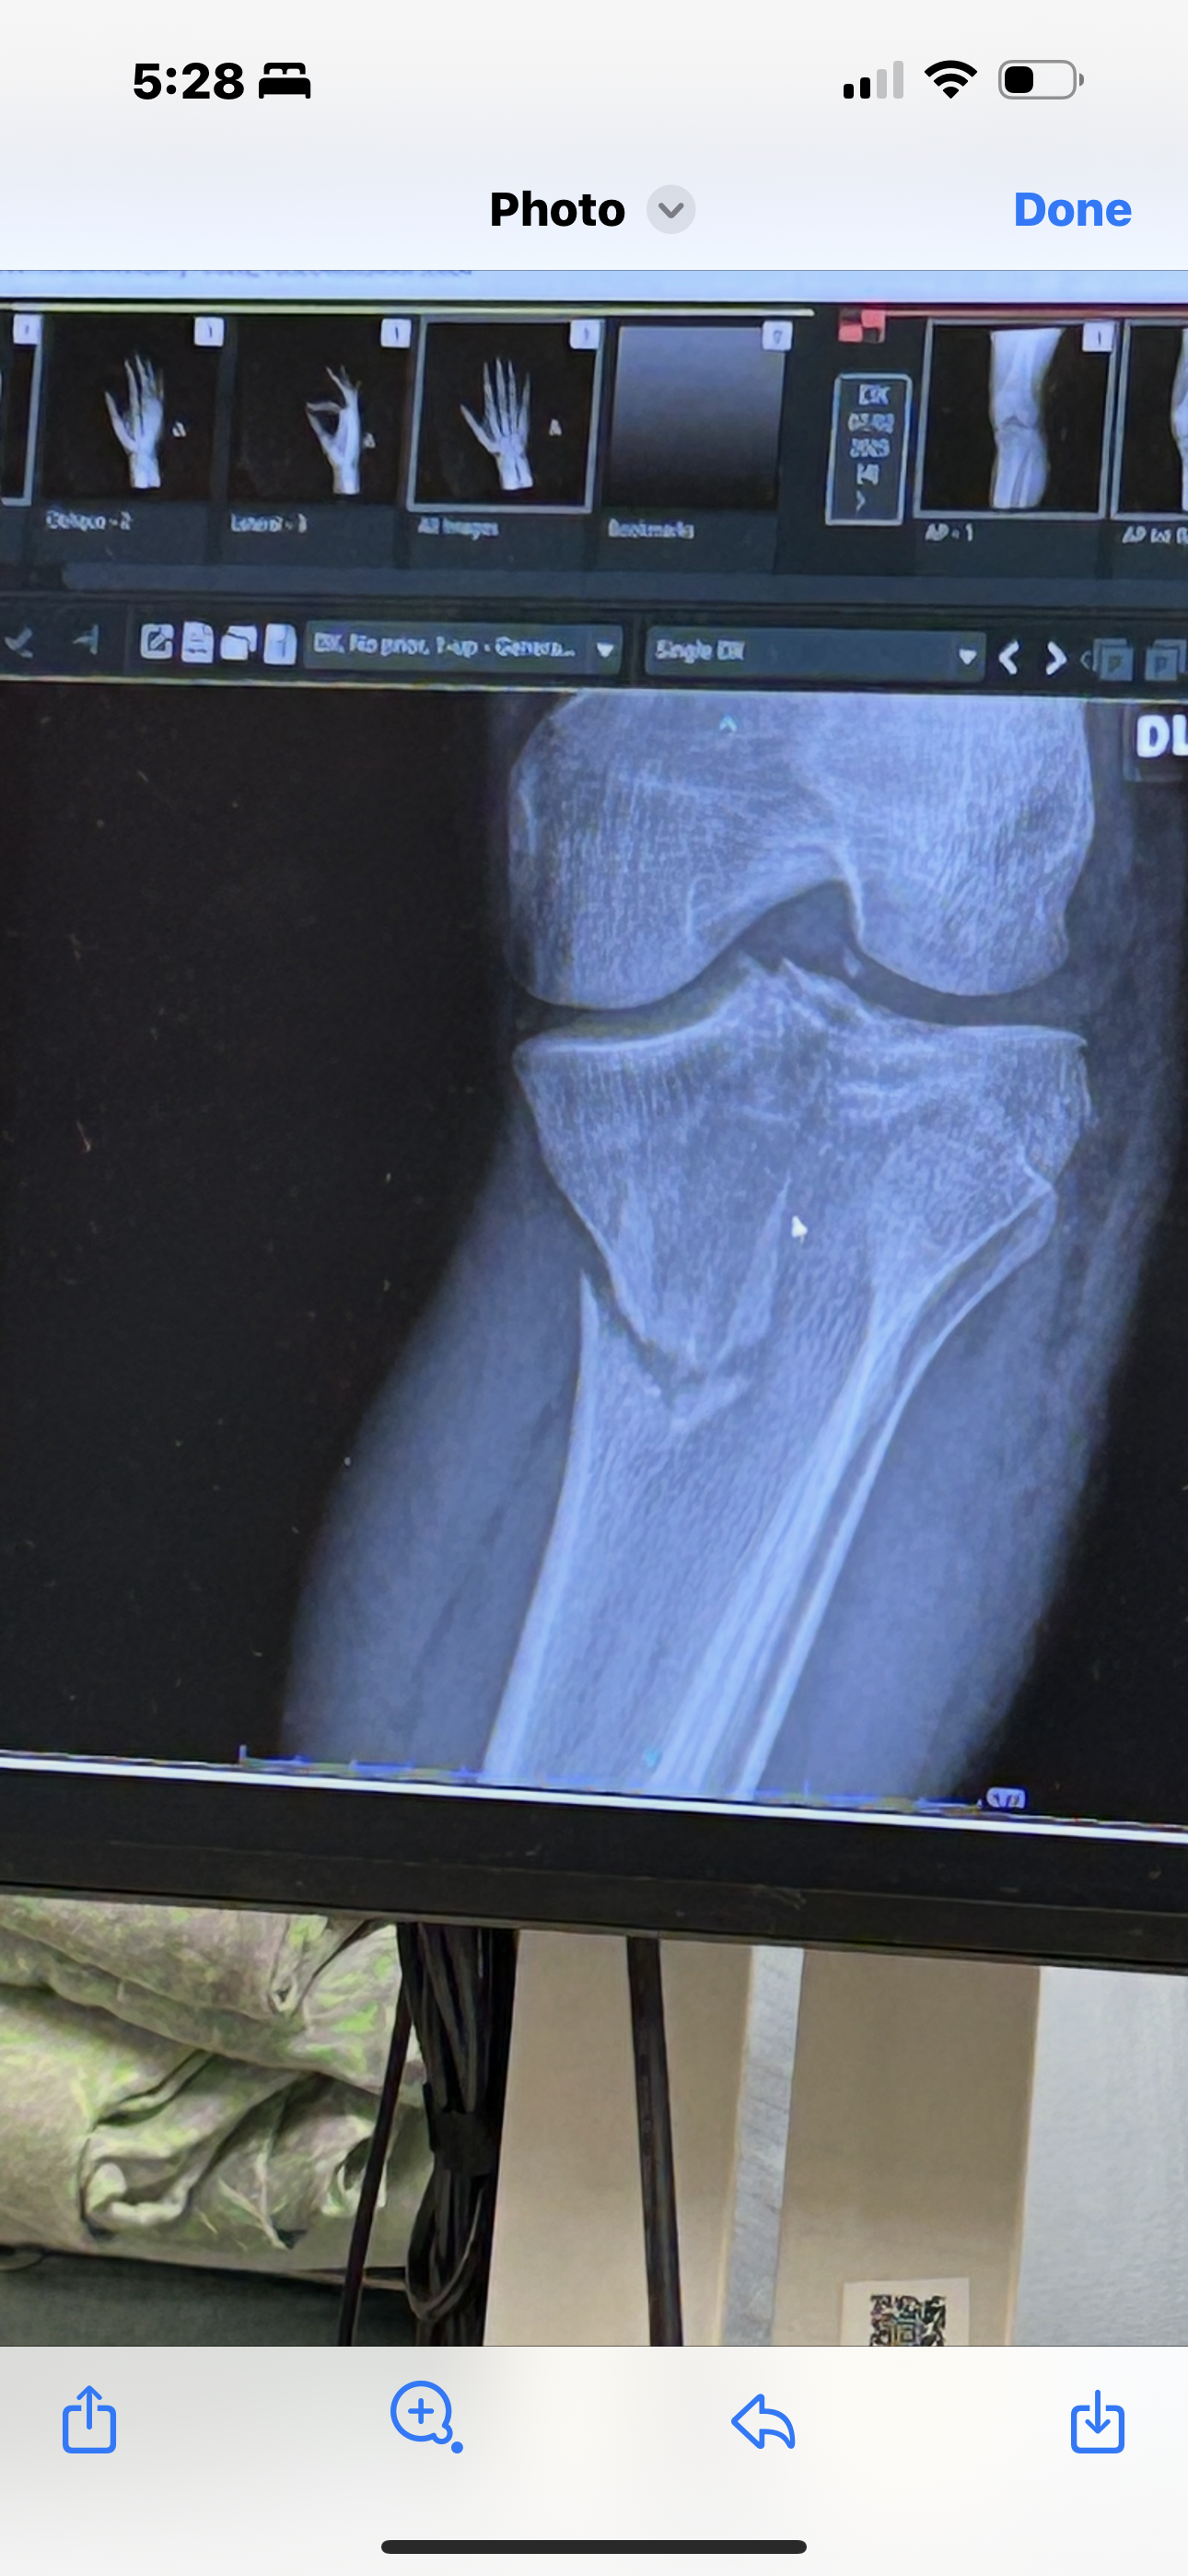

On July 2nd, what was meant to be a fun day of dirt biking with family took a sudden and serious turn. While riding trails and enjoying time with his loved ones, Ant was involved in a devastating accident. He struck a tree at high speed, injuring his right hand and suffering a broken leg when the bike looped during the crash.